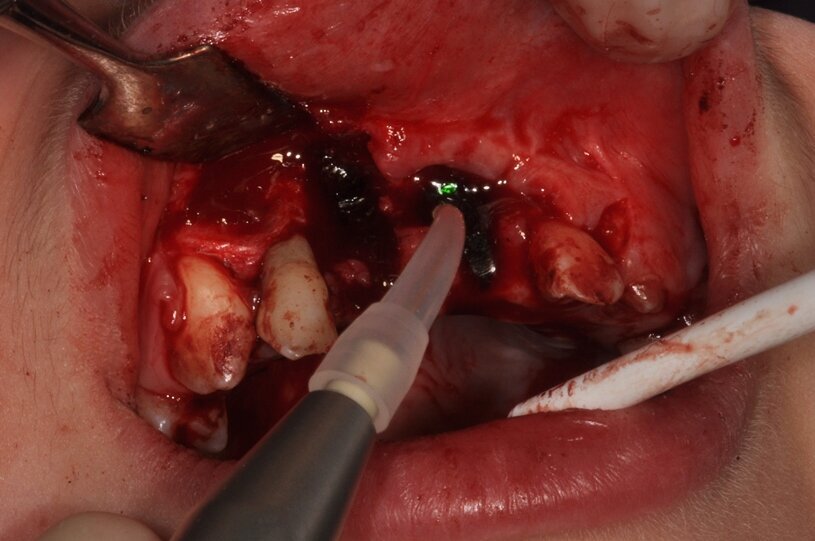

W znieczuleniu nasiękowym 1 amp. 4% Ubistesin Forte nacięto i odwarstwiono płat trapezowy śluzówkowo-okostnowy w okolicy 13 do 23. Zęby 11 i 21 usunięto w całości (Ryc. 3 i 4). Wykonano ablację kości laserem Er:YAG (LightWalker® Fotona®), (2 W, 10 Hz, 200 mJ, QSP) usuwając ziarninę zapalną, a następnie laserem Nd:YAG (LightWalker®, Fotona®), (1,5 W, 10 Hz, MSP) przeprowadzono redukcję bakterii (Fotona®).

Ryc. 4¬_Stan miejscowy po ekstrakcji i ablacji kości.